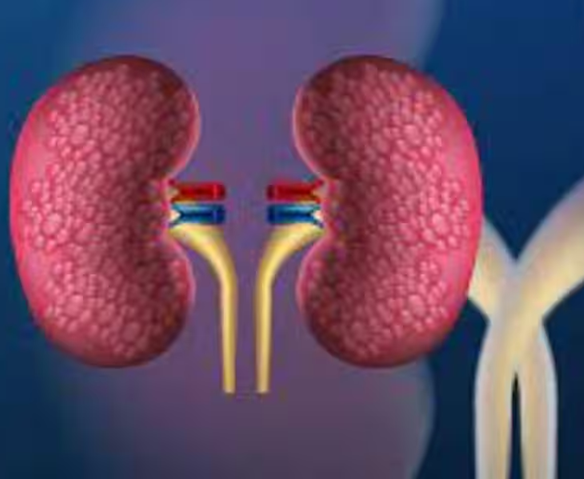

Creatinine Test For Kidneys: Due to changing diets and lifestyles, our kidneys are under significant pressure these days. Let us explain how kidney problems develop and what the symptoms are.

What Are The First Signs Of Kidney Failure? Kidneys are a vital organ in our body. They clean the blood, remove toxins from the body, and maintain water and electrolyte balance. When the kidneys fail to function properly, the body begins to display various signals. Ignoring these symptoms can be dangerous, as the condition can lead to kidney failure if not treated promptly.